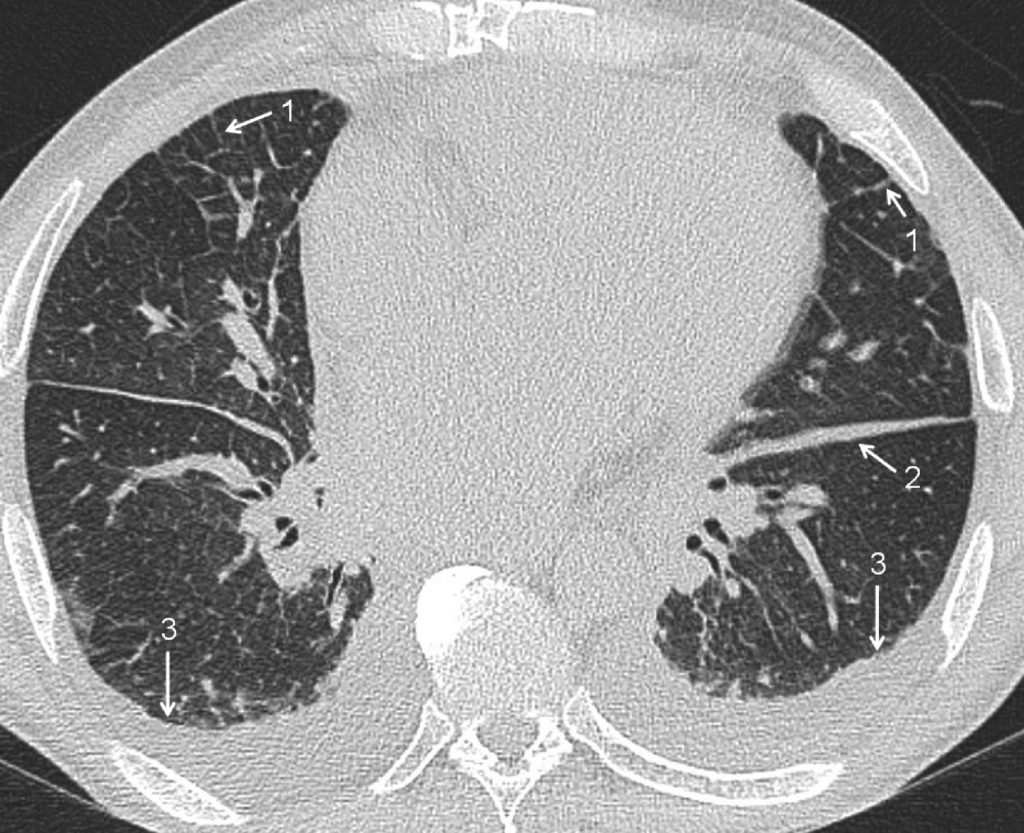

Le scanner thoracique n’est normalement pas indiqué dans l’OAP cardiogénique typique car il montre les mêmes signes que sur la radiographie : épaississement péri-broncho-vasculaire, lignes septales (équivalent des lignes de Kerley), plages de « verre dépoli » ou de condensation parenchymateuse à prédominance péri-hilaire (figures 93.2 et 93.3).

Fig. 93.2. Scanner thoracique.

Œdème pulmonaire cardiogénique. Cette coupe permet d’objectiver, outre la cardiomégalie, les signes d’œdème interstitiel : lignes septales (1), infiltration des scissures (2) et épanchement pleural bilatéral (3).

Source : CERF, CNEBMN, 2022.